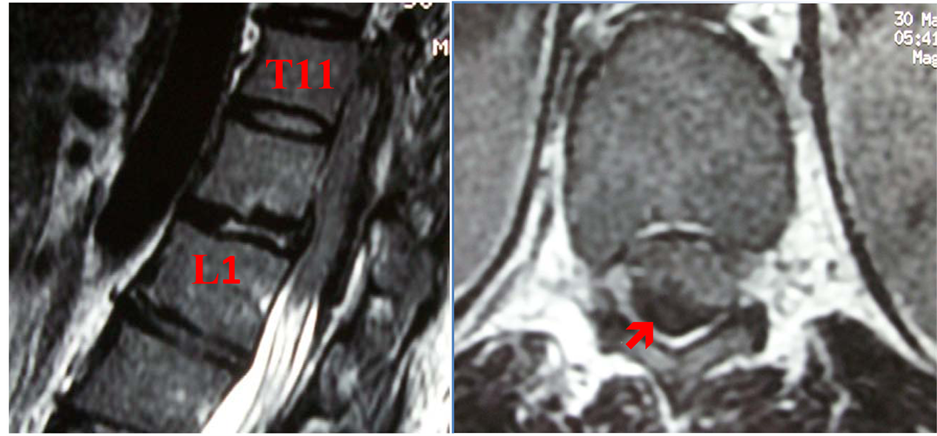

A 44-year-old woman was admitted within our department for 04 days of severe back pain complicated rapidly of bilateral lower-limbs weakness and urinary retention. Neurological examination found a complete paraplegia (0/5 stergh), with incomplete sensory deficit below the T-10 level, bowel and bladder dysfunction, decreased deep and superficial reflex. She denied any past medical history or trauma. Magnetic Resonance Imaging (MRI) with different sequences showed a large epidural mass lesion compressing the spinal cord, with slightly high signal intensity on T1-weighted images and heterogeneous low signal intensity on T2-weighted images from T11 to L1 suggesting an epidural hematoma (Figure 1). The haemostasis profile was normal and she had no history of back trauma or vascular risk factors such as arterial hypertension, diabetes mellitus, dyslipidemia and other potential bleeding disorder or medication, which can induce such blood dyscrasia.

Figure 1. PreoperativeT2-weighted MRI shows a spontaneous spinal epidural heterogeneous low signal intensity hematoma located from T11 to L1 (a) and spinal compression on the dorsal and right lateral sides (ìb).